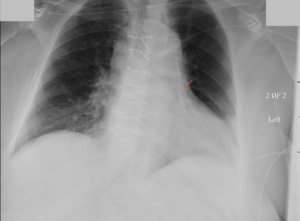

CXR CARDIOMEMS

May 1, 2021